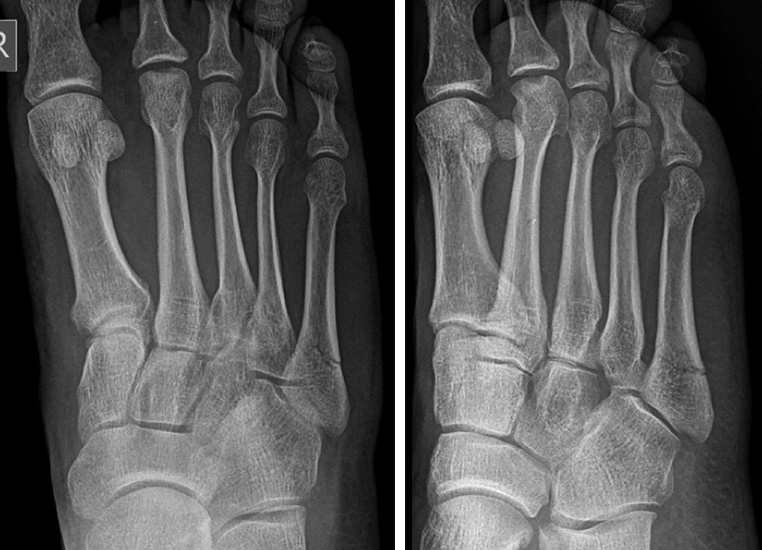

Abbildung 3

In der Literatur herrscht weitestgehend Einigkeit darüber, dass Lawrence und Botte Zone I Frakturen (Abb. 3) konservativ behandelt werden können 151617. Allerdings variieren die beschriebenen konservativen Behandlungskonzepte stark. Empfohlen werden die elastischen Wickelung bis zur Immobilisation im Unterschenkelgips/-walker, sowie die schmerzabhängige Vollbelastung bis zur vollständigen Entlastung 18. Häufig werden eine Dislokation von mehr als 2 mm, oder die intraartikuläre Fraktur (>30% der Cuboid-Metatarsalen Gelenkfläche) als Operationsindikation angesehen. Allerdings ist den Autoren keine prospektive Studie bekannt, welche ein konservatives gegen ein operatives Therapieregime verglichen hat. Egol et al. 15 publizierten eine prospektive Studie zur frühfunktionellen Nachbehandlung (schmerzabhängige Vollbelastung und festes Schuhwerk) von 49 Patienten mit einer Lawrence und Botte Zone I Fraktur (50% Intraartikulär, 32% > 2mm Dislokation). 94% der Patienten konnten nach 6 Wochen den Fuß voll belasten. Die mittlere Zeit der Arbeitsunfähigkeit betrug 22 Tage. Die volle Sportfähigkeit war bei 86% der Patienten nach 6 Monaten, bei allen Patienten nach einem Jahr erreicht. Weder der Grad der Dislokation noch die intraartikuläre Beteiligung hatten einen signifikanten Einfluss auf diese Zielparameter.